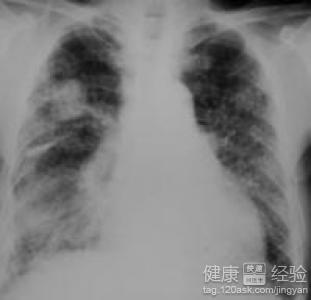

心絞痛和心梗有區別     正常情況下,心絞痛是一過性的,持續一般不會超過15分鐘。但是,如果不在疼時做心電圖,平時心電圖也很難顯露端倪,很可能誤診為胃疼。 心絞痛和心梗有區別 飲用綠茶可有效預防心肌梗死   因為僅僅從症狀上,沒有醫學知識的人確實很難分辨是普通的胃疼還是心絞痛引起的胃痛,需要借助病史和臨床檢查。所以,避免心絞痛被誤診的關鍵還是醫生和病人自己對心梗的發生有提防的意識。     心絞痛和心梗都是冠狀動脈硬化性心髒病,簡稱“冠心病”的症狀。從程序上說,心絞痛是冠心病的常見症狀,心梗是冠心病的危急症狀,心絞痛不斷加重最終會發展成心梗。     飲用綠茶可降三高有效預防心肌梗死     綠茶現已成為白領們辦公桌上不可少的飲料,不但可以抗電腦輻射,還能幫助消化,起到清腸減肥的作用。這只是人們認識的比較多的,可是你知道飲用綠茶可以降低三高,還能降脂,降了三高就意味著人們得心肌梗死的機率就小了一些,這些都不是吹的,一些國外的研究學家們都可以證明。     據美國心髒病雜志日前報道,日本一項新的研究顯示,飲綠茶能減少心肌梗死的危險性。盡管那些每天飲一杯或更多綠茶的研究對象和不飲綠茶者相比,患冠心病的可能性並沒有降低,但是心肌梗塞的可能性大大降低。     saitama國立預防醫學院的合作研究者yukihikomo心肌梗塞yama博士說,我們發現在日本心肌梗塞的發生率在飲用綠茶者中降低,顯示有規律地飲用綠茶可能起到了防止發生心肌梗塞的保護作用。     飲綠茶可降低三高     研究表明,綠茶能夠幫助改善消化不良,比如由細菌引起的急性腹瀉,喝綠茶可減輕病況。綠茶還有減肥的功效,經常接觸油漆、電腦等群體可多飲綠茶;喜歡抽煙喝酒的人可多飲綠茶。而對於老年人來講,如果你是個老茶客,最好選用冷泡法泡茶,即用涼白開泡茶,這樣可降“三高”。綠茶不能空腹喝,否則會“茶醉”;感冒者、腸胃不好者不宜喝綠茶。